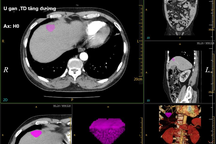

Nước ta có tỷ lệ nhiễm siêu vi viêm gan B rất cao, chiếm hơn 10% dân số. Do vậy, những đối tượng dễ mắc ung thư tế bào gan bao gồm người bệnh viêm gan siêu vi B và C mạn tính, xơ gan cần được theo dõi, khám sức khỏe định kỳ mỗi 6 tháng 1 lần, thực hiện siêu âm bụng, các xét nghiệm phát hiện ung thư gan như AFP, PIVKAII... Đến khi phát hiện có khối u bất thường trong gan, người bệnh phải được kiểm chứng chính xác bằng phương pháp chụp X-quang cắt lớp điện toán (CT scan), cộng hưởng từ (MRI) hoặc sinh thiết gan...

Trên thực tế, nhờ chiến lược tầm soát ung thư tế bào gan sớm, các bác sĩ có thể phát hiện kịp thời các khối ung thư mới xuất hiện, nhờ vậy có thể áp dụng các phương pháp điều trị hiệu quả, triệt để cho người bệnh như: phẫu thuật cắt bỏ phần gan bị ung thư, dùng nhiệt, sóng cao tần phá hủy khối u, nút tắc mạch máu nuôi khối u hoặc ghép gan… Nhờ vậy sẽ mang lại kết quả lâu dài, cải thiện tiên lượng sống cho người bệnh.